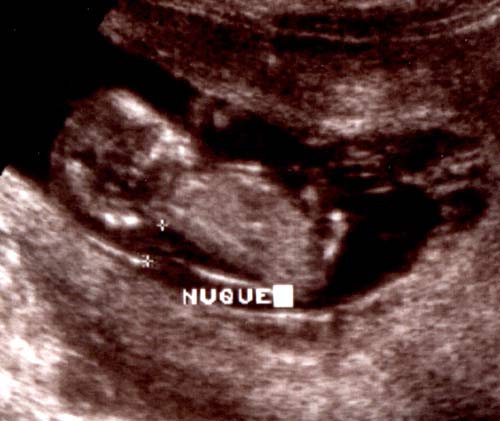

Clarté nucale d'épaisseur anormale (7 mm)

à 11 semaines d'aménorrhée